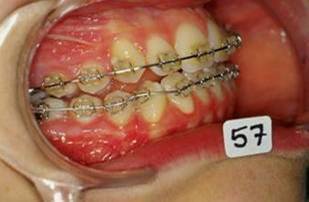

En fouillant dans mes cas j'ai trouve celui ci qui presente une beance assez importante. Je me suis rappele qu'un certain message etait lance il y a qq temps a propos d'un enfant qui presente une beance et de savoire comment faire dans ce cas. Je pense qu'il est interessant de voir comment les uns et les autres prennent en charge ce type de cas. Il s'agit d'un fille de 12 ans, succion de pouce, interposition linguale totale, beance de molaire a molaire, respiration mixte, incompetence labiale au repos, fonction labiale serree. Le total quoi!!! Voici la premiere serie de photos

4- Collage de l'arcade sup, presque 6 mois apres et voici le photo apres seance de college

Collage bas fait presque 3 mois apres le haut, avec des elastiques verticaux pendant 3 semaines seulement. Et voici les photos, la suite je vous en passe car il s'agit de simple finition.

P.S. photos au moment du collage bas